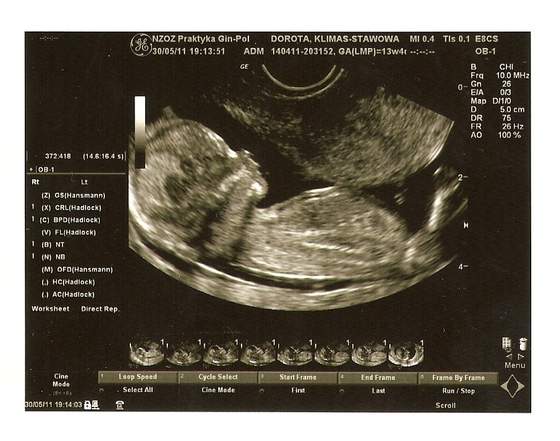

wiec tak moje drogie byłam u lekarza badania prenatalne wyszły dobrze więc nie mam czym się martwić -czego życzę wszystkim przyszłym mamusią wizyta trwała troszkę dłużej niż zwykle bo oglądałam moją kluskę co wyprawia w brzuszku

mój maluszek mierzy 7,10 cm więc miałam już na co popatrzeć :-)przeżyłam ta wizytę jak bym pierwszy raz na USG była

oczywiście zdjęcia też musiałam mieć więc podzielę się z wami moim szczęściem

zadarty nosek

no i te Ustka normalnie aż mi łezki u gina poleciały ..